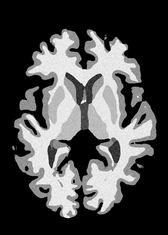

4.2 Registration to a 100 micron ex-vivo brain MRI volume

To showcase the efficacy of our method on real large scale images, we register a 250 in-vivo MRI image (Lüsebrink et al., 2017) to a 100 ex-vivo FLASH human brain volume (Edlow et al., 2019). This represents an inverse problem with more than 11.2B optimizable parameters (compared to 20M for clinical datasets), or 44.8GB of GPU memory. The entire problem does not fit on most GPUs, necessitating distributed multimodal registration. We optimize a composite transform - affine followed by a diffeomorphic mapping; details can be found in Section E.1. Multimodal deformable registration took 58 seconds on 8 NVIDIA A6000 GPUs, which is unprecedented at this resolution. Fig. 6 shows qualitative results, highlighting the ability to register highly detailed structures such as cerebellar white matter; these structures are not visible at macroscopic scales. The resultant advantages of performing registration at this scale can allow researchers to characterize the neuroanatomy at microscopic resolutions and allow morphometric analysis of cortical layers and subcortical nuclei among other structures.